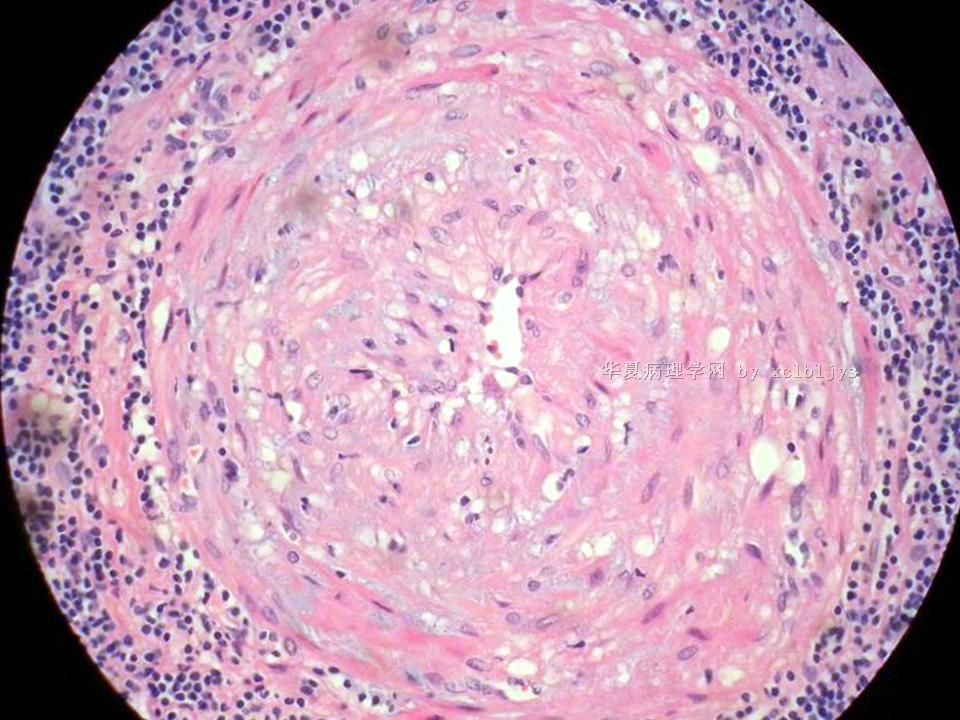

| 以下是引用xclbljys在2010-12-22 17:20:00的发言: 本例我们科室医生有两种意见:一种是炎性假瘤;第二种意见是炎性假瘤伴局限性Wegener肉芽肿。 依据是眼眶内肿块含有大量的动脉内膜炎改变,浸润的炎细胞有淋巴细胞、浆细胞、嗜中性粒细胞和嗜酸细胞等,如图16所示,炎细胞已经浸润动脉壁全层,应符合坏死性小动脉炎,但尚不能确定动脉壁弹力纤维层的破坏。 请各位老师点评! Wegener肉芽肿多发生在上呼吸道、肺、肾脏和皮肤等器官与组织。坏死性血管炎需证实有纤维素样坏死。小动脉炎多在皮肤病变比较明显。本例的小动脉炎或许是炎症引起的继发性改变。需要完善病史,查血免疫指标,看有没有系统性疾病。如果没有系统性疾病,还是考虑慢性炎症继发小血管炎。

血管炎是正常营养/供给血管的炎症性病变,而不是增生血管的炎症。血管炎往往有明显的临床相应症状,如皮疹。典型的Wegerner肉芽肿病有三联症(上呼吸道、肺、肾脏病变)。血管炎不仅是有炎症细胞,同时有血管壁的变性、坏死(纤维素样), 内皮细胞的变质和增生,炎症细胞浸润(包括中性粒细胞、淋巴细胞、组织细胞、嗜酸性细胞、巨细胞等)。不同类型的血管炎累及的血管大小、炎症细胞的类型、有无肉芽肿改变都不相同。血管炎的病因可以是过敏、自身免疫、胶原性疾病、感染等多种因素。